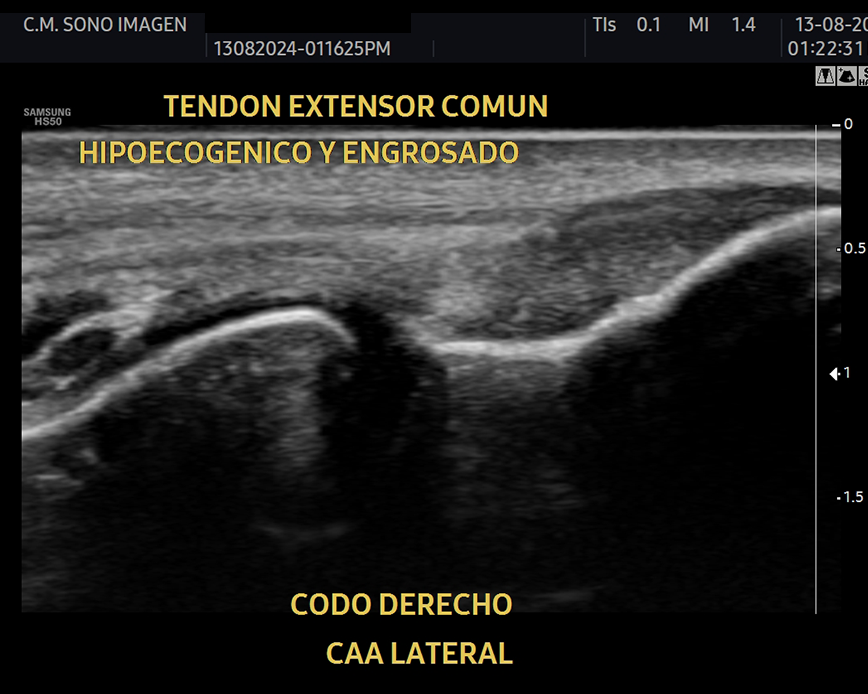

Es un procedimiento no invasivo y seguro , incluido niños, ya que no usamos radiación ionizante. Permite realizar un diagnóstico en tiempo real y podemos evaluar tendones, músculos, ligamentos, articulaciones y nervios.

¿Qué ecografías realizamos?

- lesiones de tejidos blandos: tendinosis, desgarros ligamentosos, rupturas meniscales.